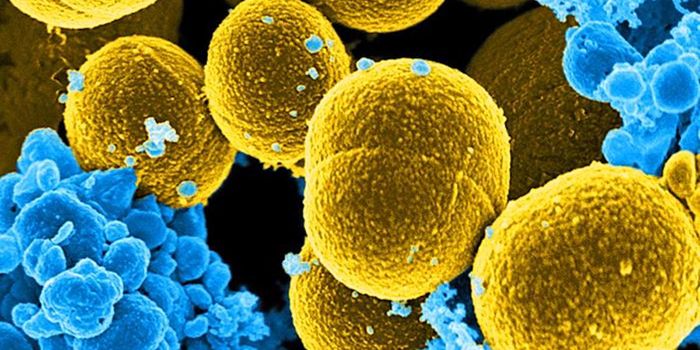

SEP 17, 2021Cell & Molecular BiologyMRSA (methicillin-resistant Staphylococcus aureus) is a well known superbug, a pathogenic microbe that can cause serious ...